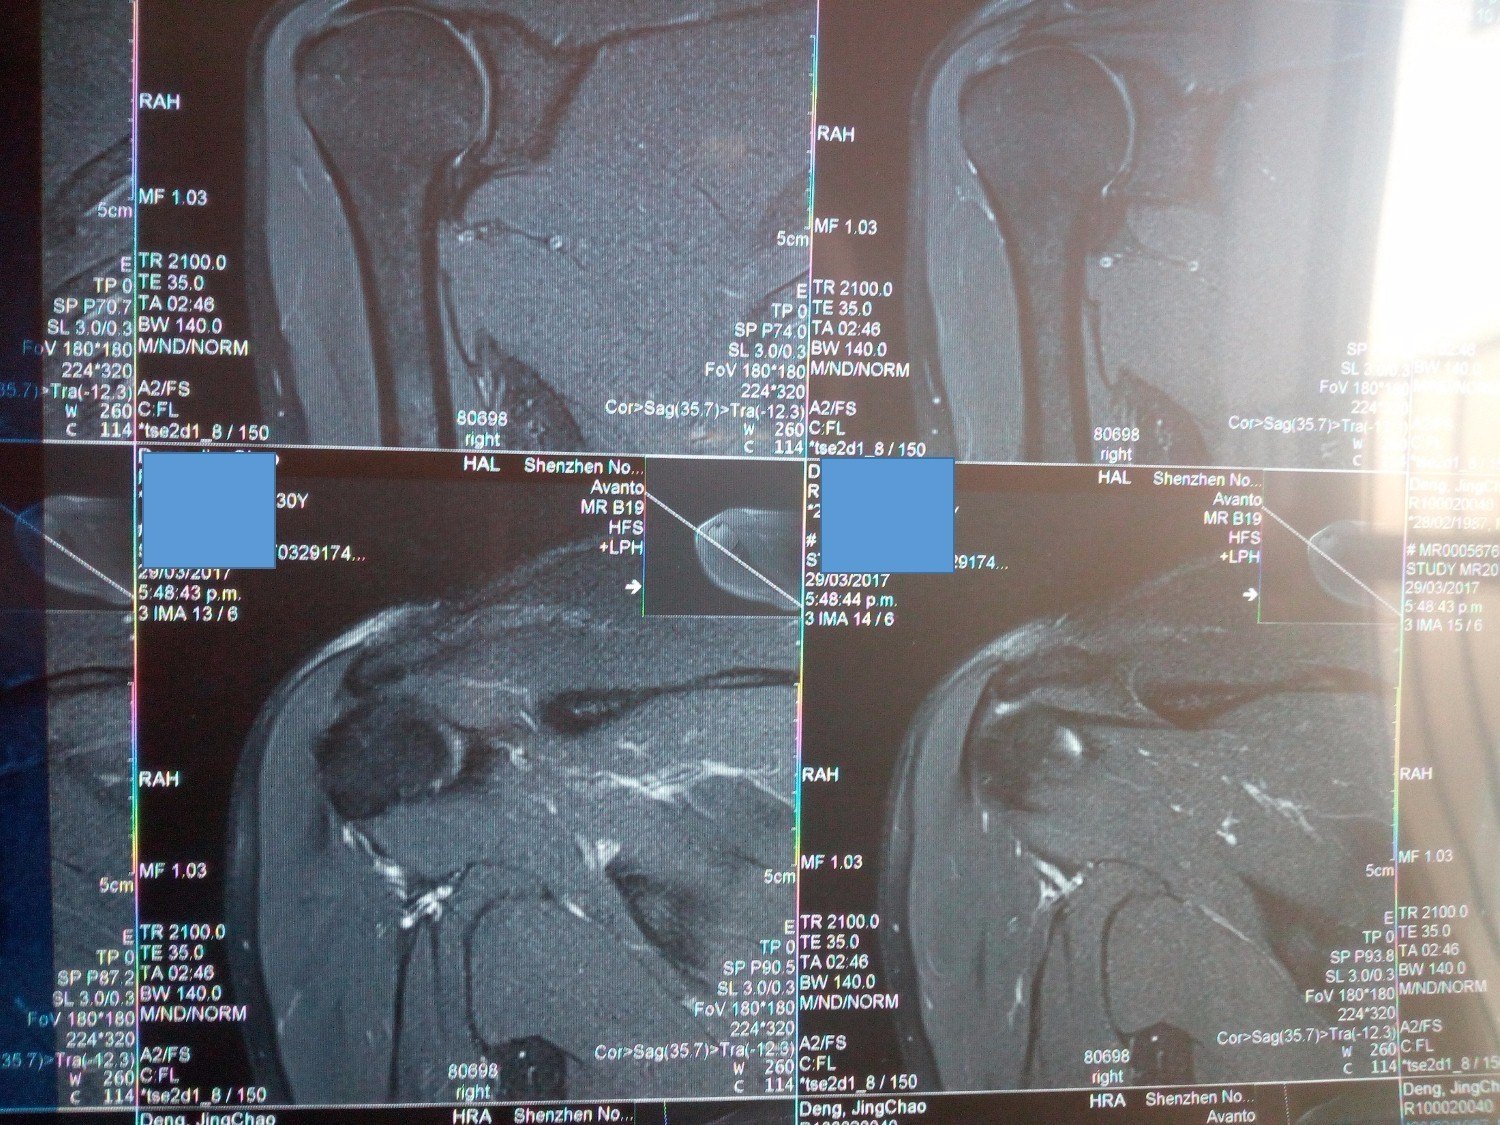

3.MRI(以膝关节为例)

由于MRI和CT一样也 是三维成像,包括矢状面,冠状面和横断面三个层面的扫描。一张MRI片子也是包括医院、姓名、性别、年龄、检查日期、侧别、扫描序列等信息的。不同的示MRI在片子上是信号的高低(CT时密度的高低),也就是说有T1和T2序列(T2序列表现为关节积液是高信号-发白;T1序列表现为关节积液为低信号—发黑或发灰)。因此MRI上不仅有矢状面、横断面和冠状面,还有T1序列和T2序列。

一般来说T2序列更能反应损伤情况,所以平时观察T2序列的图像要更仔细。T1序列主要观察解剖结构,有些医院一般不常规做。